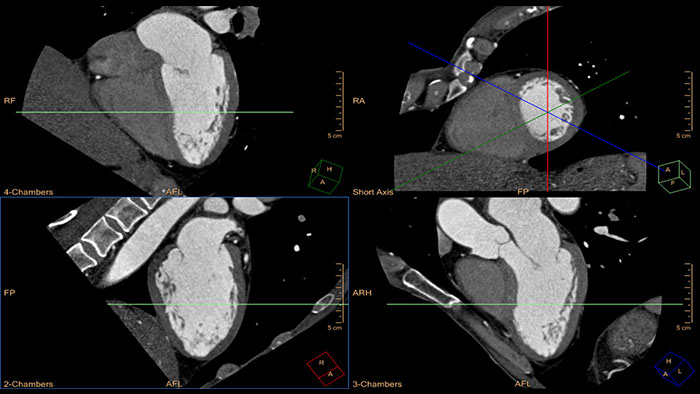

Quick cardiac visualization

Provides a set of tools for the visualization of one or multiple cardiac phases using original images or MPR\MIP images in axial, coronal, sagittal or dedicated cardiac axes (short axis, horizontal long axis, and vertical long axis).